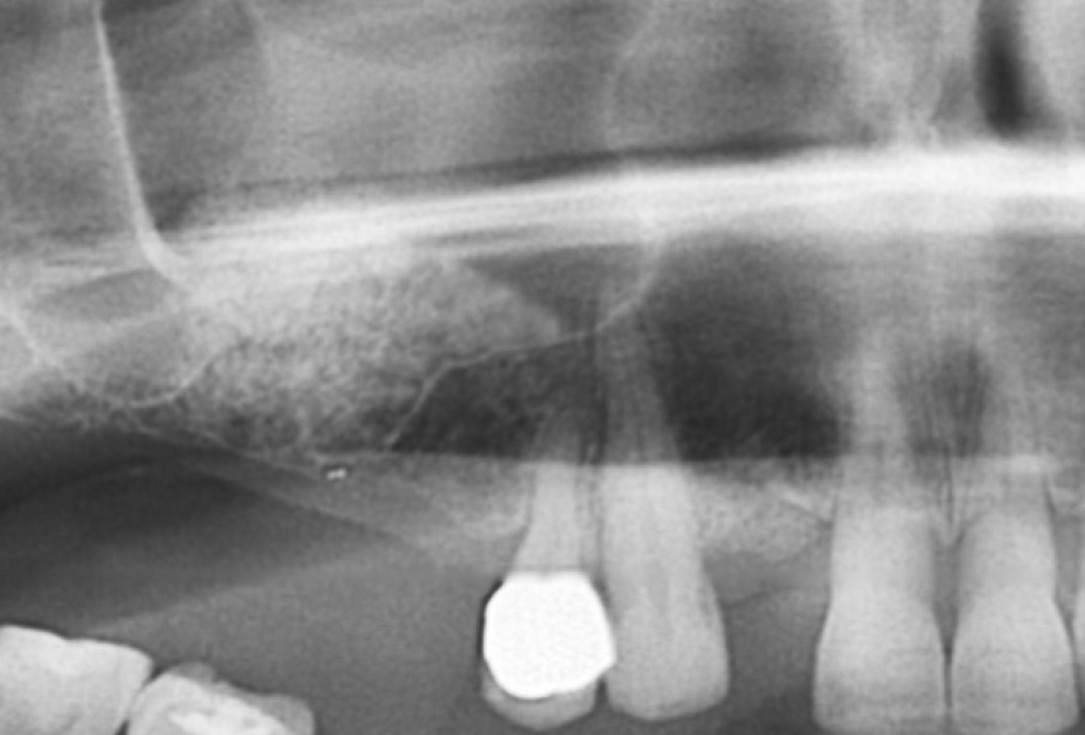

DVT control after sinusitis surgery, residual bone height 1 mm